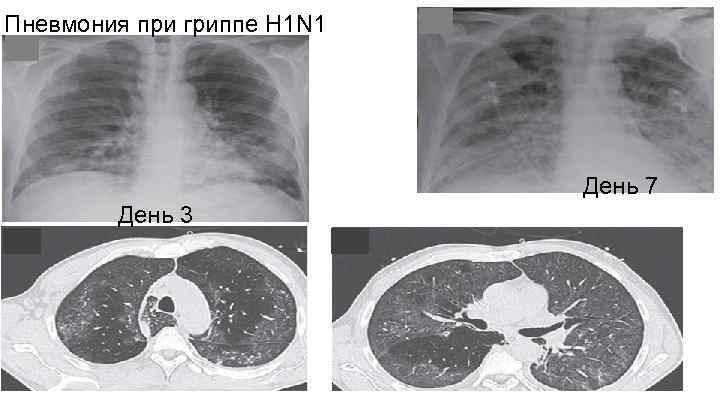

Пневмония при гриппе H 1 N 1 День 7 День 3